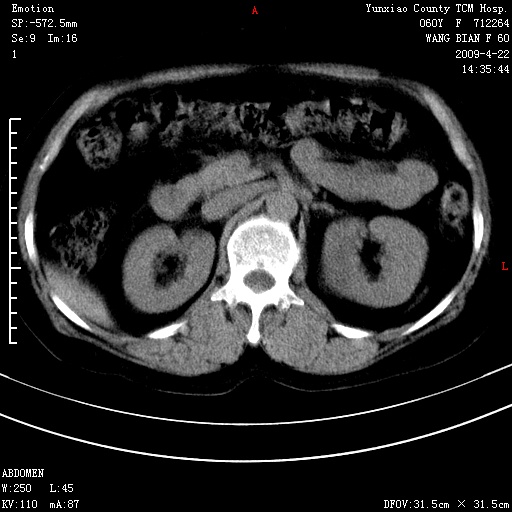

蛛网膜颗粒压迹 左肾低密度影囊肿可能。

不出外肾癌,强化下看

2、左肾囊肿。

脑正常,肾有事,须强化,再定性.

1、头颅未见明显异常。2、左肾囊肿可能。建议增强

1、枕骨蛛网膜粒压迹。2、左肾囊肿可能。建议增强

头颅未见明显异常。左肾囊肿。

1)枕骨蛛网膜粒压迹。2)左肾囊肿可能。

不出外肾癌,强化下看,枕骨蛛网膜粒压迹。

2、左肾囊肿可能性大。